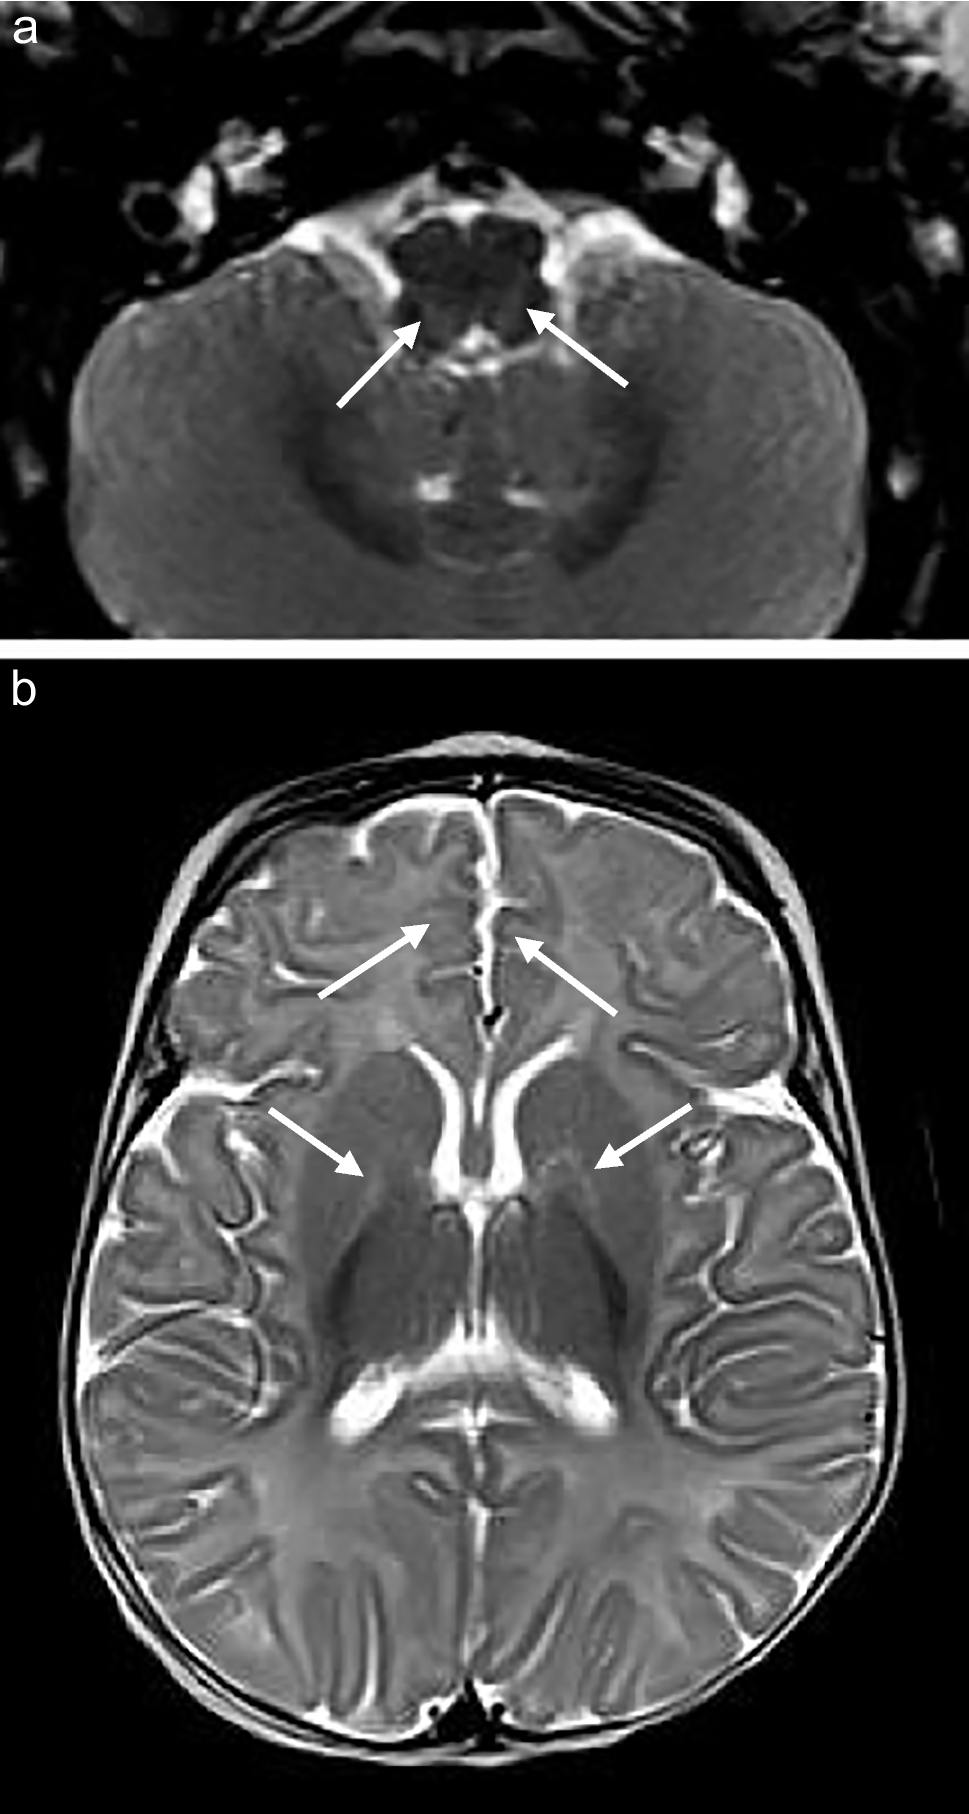

Fig. 5

A 5-month-old male infant with genetically confirmed MPV17-MDS. a Axial T2-weighted image shows hyperintense signal in the reticular formation of the proximal cervical cord (arrows). b Axial T2-weighted image shows hyperintense signal in the reticular formation of the medulla (arrows). c Axial T2-weighted image shows hyperintense signal in the globus pallidi. d Axial diffusion -weighted imaging shows restricted diffusion in the thalamic pulvinars (arrows)

Basal ganglia and thalamus

Signal and volumetric alterations in the basal ganglia were identified in five of eight (62.5%) patients (Figs. 2, 4, 5 and 6). One of the neonates had isolated, symmetrical lentiform nucleus involvement. The caudate heads were symmetrically oedematous with facilitated diffusion, while the globus pallidi, also swollen, displayed restricted diffusion. This may reflect different stages of evolution of the cerebral lesions with pseudonormalisation of DWI in the globus pallidi. The 5-month-old infant had symmetrical diffusion restriction in the thalamic pulvinars without accompanying basal ganglia changes. The 4-month-old, 5-month-old, and two 8-month-old children had MRI studies which demonstrated T2 hyperintense signal in the globus pallidi, confined to the medial or posteromedial aspects in three of the four cases.